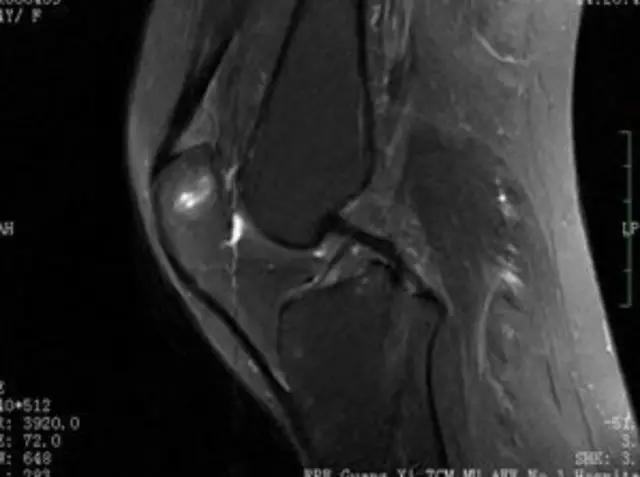

下图是同一个病人的MRI照片,MRI显示的内容更多,包括骨与软组织等,很多早期的、细微的病变都能清晰显示,其诊断报告对病人造成的影响也更大!

我们可能都不熟悉T1、T2,怎么办?当我们发现有问题后,利用照片上图像的对比,推测病变的可能也是一种诊断方法。病例:黄XX,女,39岁,左膝关节反复交锁1年。图1:肿物信号与骨信号一样图2:肿物信号与骨信号一样图3:肿物信号与骨信号不一样 肿物应该与骨相关,但不是骨性,推断:膝关节滑膜软骨瘤。手术后得到证实。